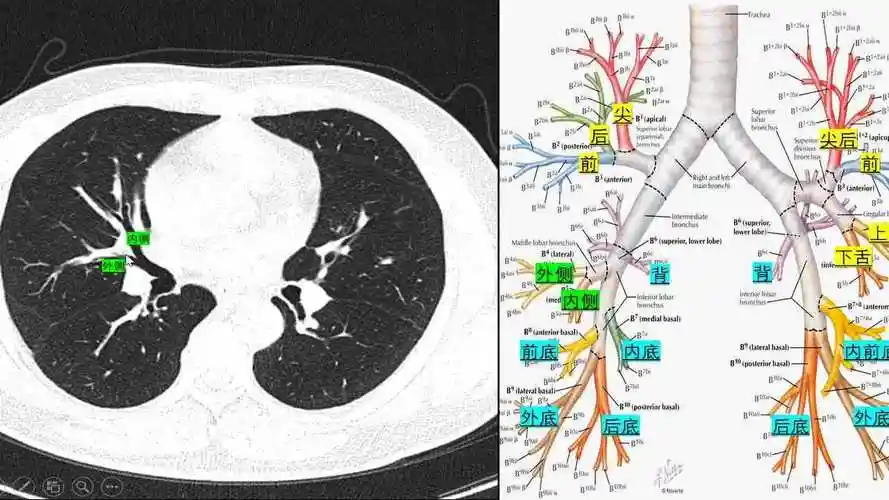

肺段分布及重要血管ct读片轻松掌握